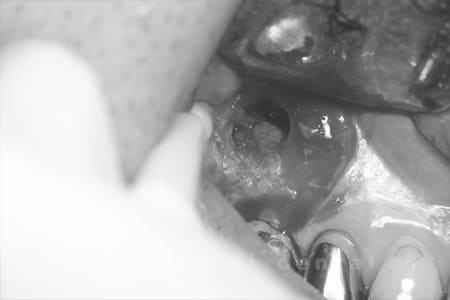

他院で治療した歯が腫れていて、様子を見るように言われたが、なかなか治らない、とのことでご来院された患者さんです。歯根端切除術を行い、腫れもなくなり、経過良好です。

<リスク・副作用>

外科手術のため、術後に出血、痛みや腫れ、違和感を伴います。口腔内の状態によっては適応できないことがあります。歯根端切除で治らなければ抜歯を検討しなくていけない場合もあります。